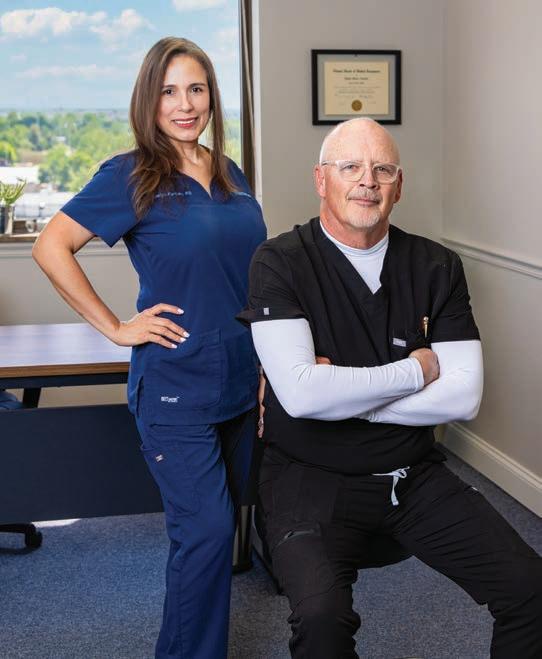

WE ASKED LOCAL PHYSICIANS WHO THEY’D RECOMMEND TO LOVED ONES IN NEED OF MEDICAL CARE. THE RESULTS ARE THE PEER-CHOSEN TOP DOCTORS OF 2025.

WRITTEN BY JO JOLLIFF

Doctors Doing Good 74 Inside Citizen Memorial’s Growth

SUMMARY. DataJoe Research is a so ware and research company specializing in data collection and verification, and conducts various nominations across the United States on behalf of publishers. To create the “top doctors” list, DataJoe Research facilitated an online peer-nomination process, also referencing government sources. In addition, DataJoe o en conducts media analysis through Internet research to factor in public perception. DataJoe then tallied the nominations per category for each doctor to isolate the top nominees in each category. A er collecting nominations and factoring additional information from the media analysis, DataJoe checked and confirmed that each published winner had a current, active license status with the state regulatory board. If we were not able to find evidence of a doctor’s current, active registration with the state regulatory board, that doctor was excluded from the list. In addition, any doctor who has been disciplined, up to the time-frame of our review process for an infraction by the state regulatory board, was excluded from the list. Finally, DataJoe presented the tallied result to the magazine sta for final review and adjustments.

FINAL NOTE. We recognize that there are many good doctors who are not shown in this representative list. This is only a sampling of the huge array of talented professionals within the region. Inclusion in the list is based on the opinions of responding doctors in the region and the results of our research campaign. We take time and energy to ensure fair voting, although we understand that the results of this survey nomination are not an objective metric. We certainly do not discount the fact that many, many good and e ective doctors may not appear on the list.

DISCLAIMERS. DataJoe uses best practices and exercises great care in assembling content for this list. DataJoe does not warrant that the data contained within the list are complete or accurate. DataJoe does not assume, and hereby disclaims, any liability to any person for any loss or damage caused by errors or omissions herein whether such errors or omissions result from negligence, accident, or any other cause. All rights reserved. No commercial use of the information in this list may be made without written permission from DataJoe.

Questions? For research/methodology questions, contact the research team at surveys@datajoe.com.